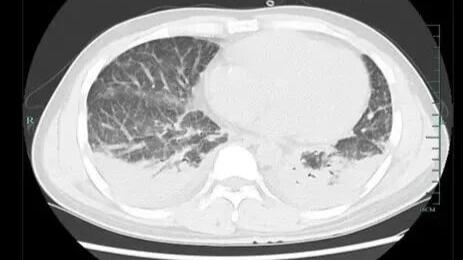

壮哥经检查:胸部CT双肺弥漫性病灶,血氧饱和度指标不到70%。“重症肺炎,I型呼吸衰竭。再拖下去有生命危险!”他随即被安排住院治疗,并做了基因检测,揪出了真凶——马尔尼菲篮状菌。

壮哥的肺部情况